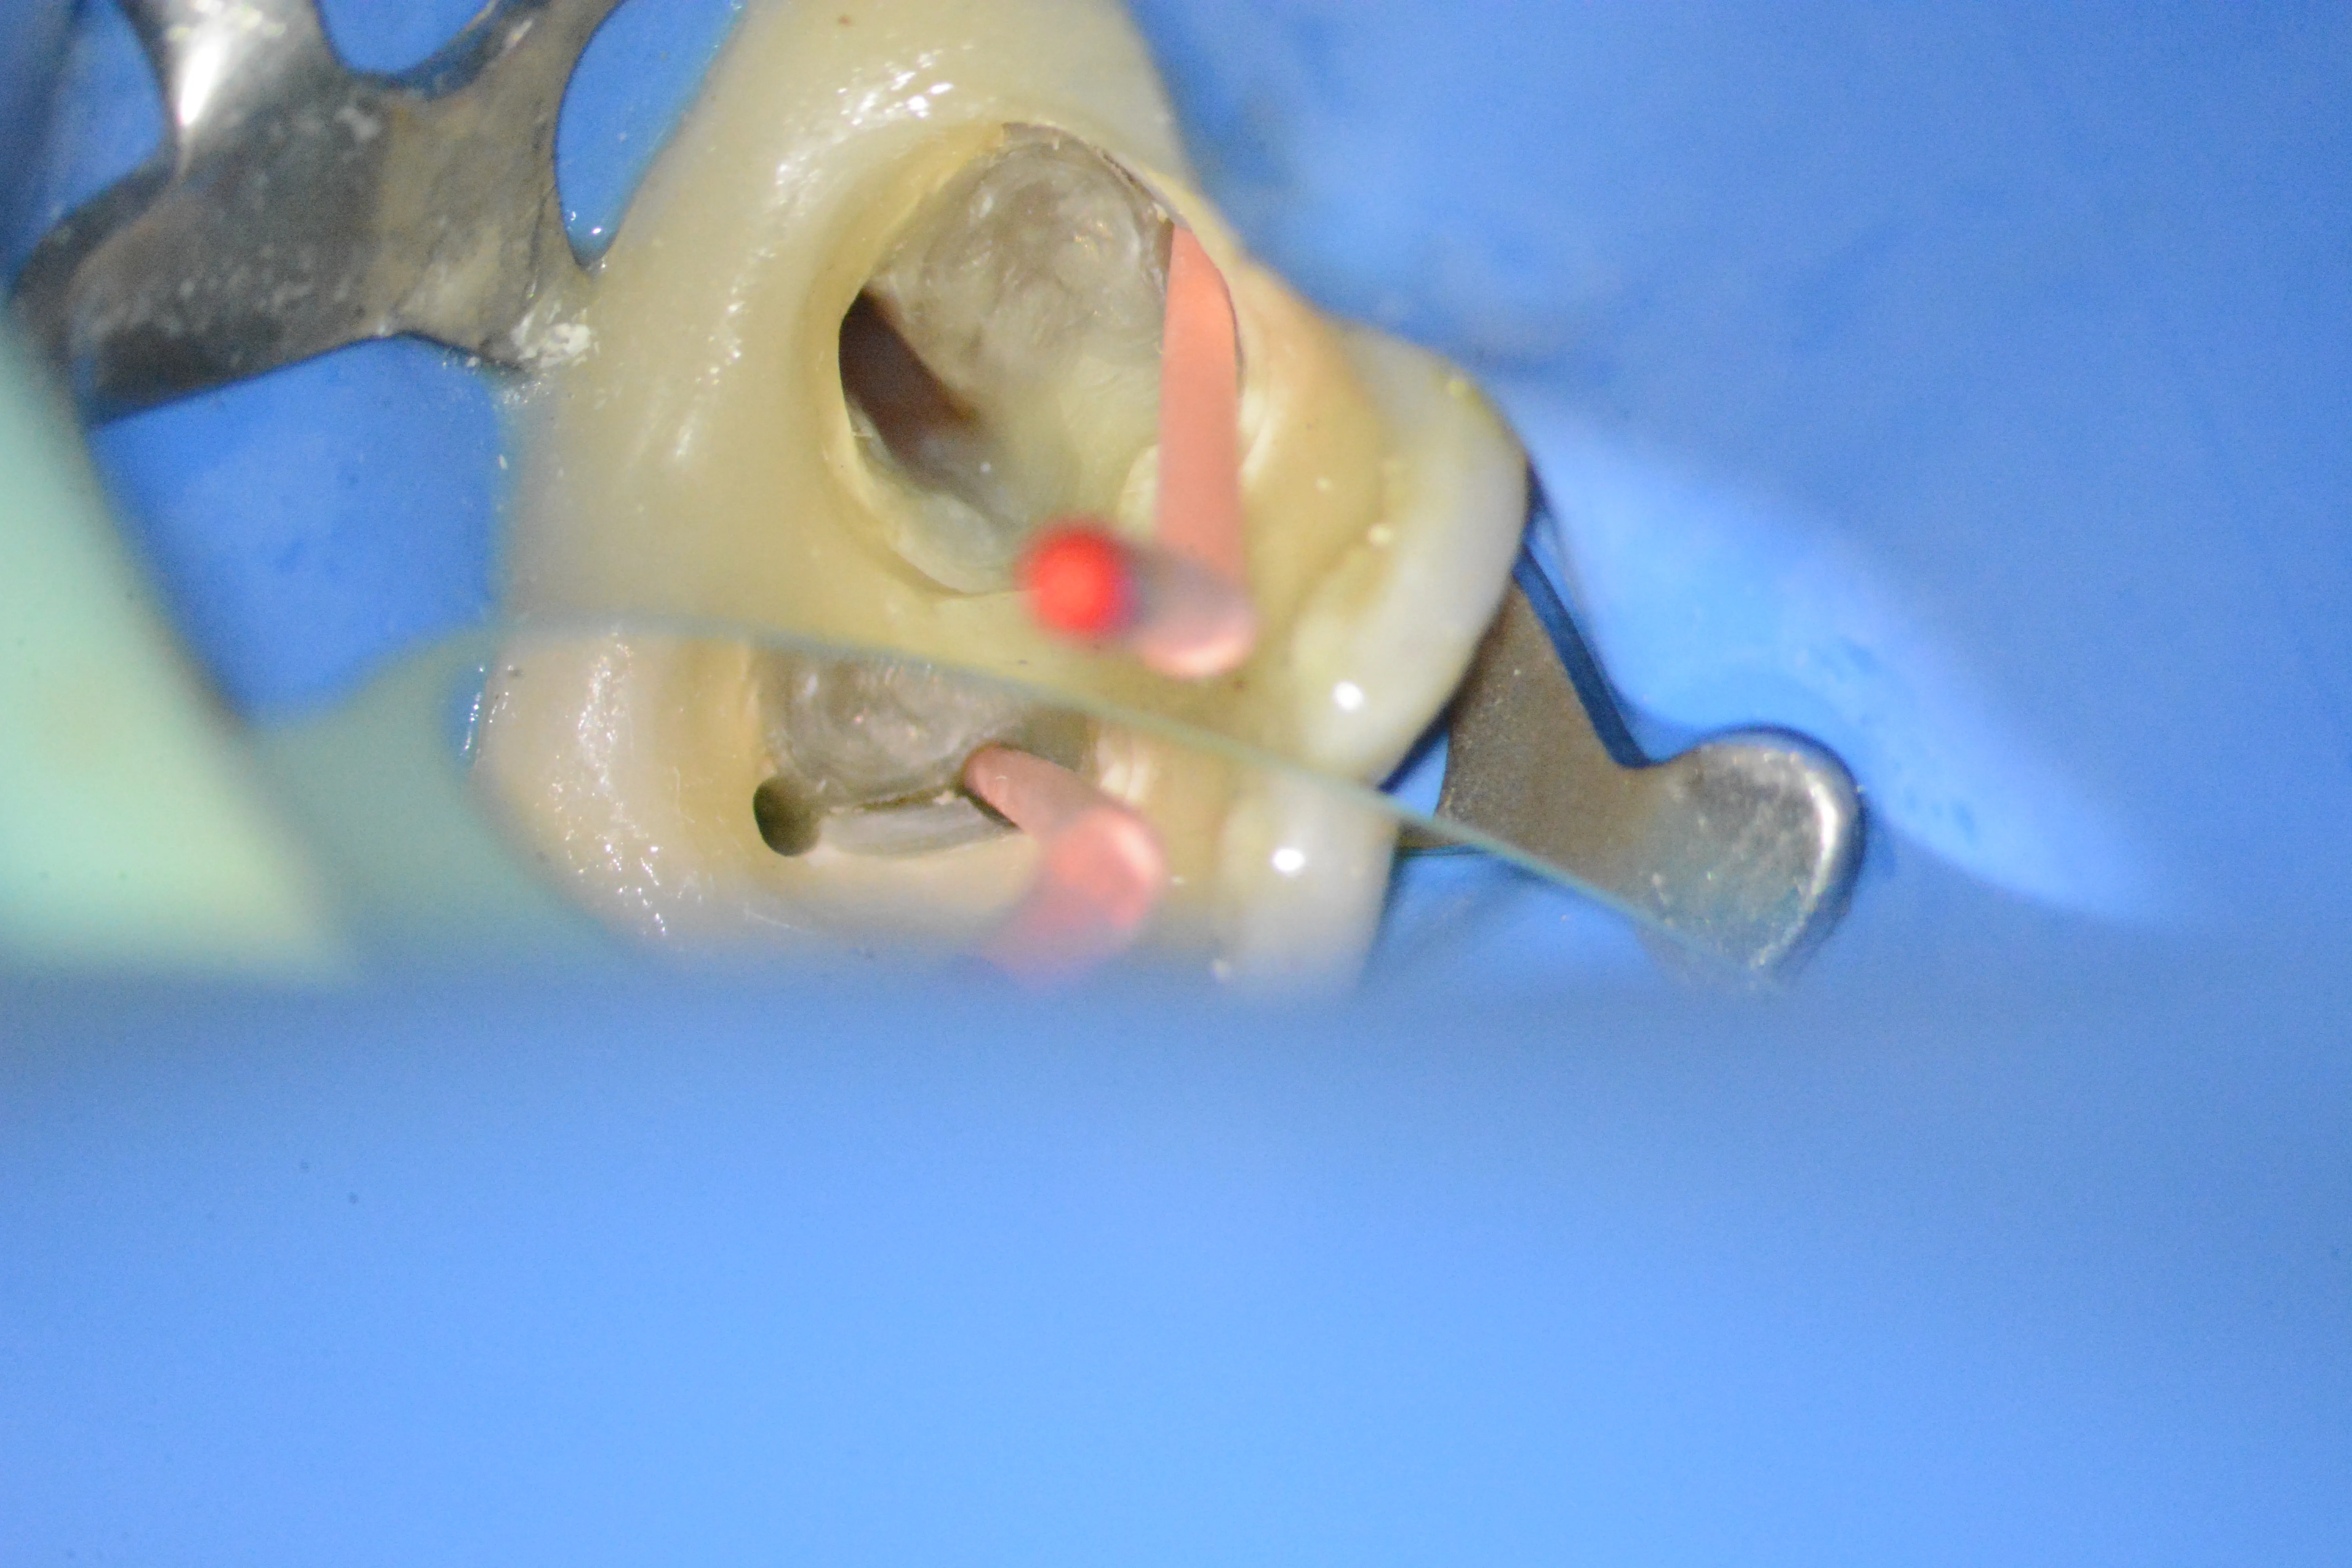

9 – Stabilirea conurilor master